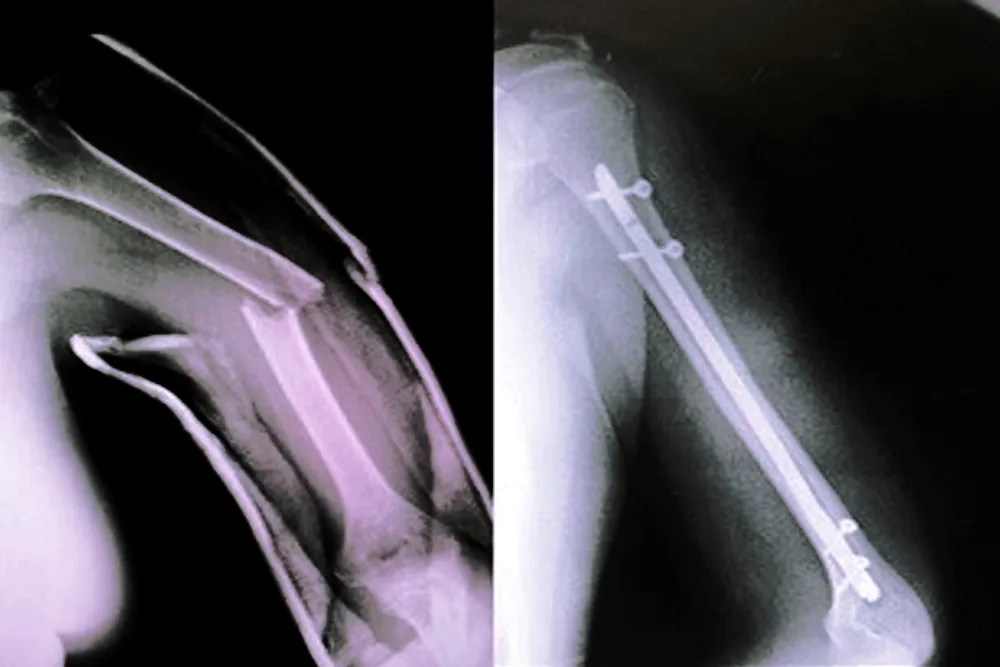

LESIONES y FRACTURAS COMUNES QUE TRATAMOS

Egresado de la Universidad San Luis Gonzaga de Ica, con estudios de posgrado en la Universidad Federico Villarreal. Con más de 15 años de experiencia, el Dr. Vladimir Inca se ha especializado en el tratamiento de fracturas, lesiones articulares y cirugías de prótesis. Su enfoque se basa en brindar atención personalizada y soluciones efectivas para mejorar tu calidad de vida y recuperar tu movilidad.